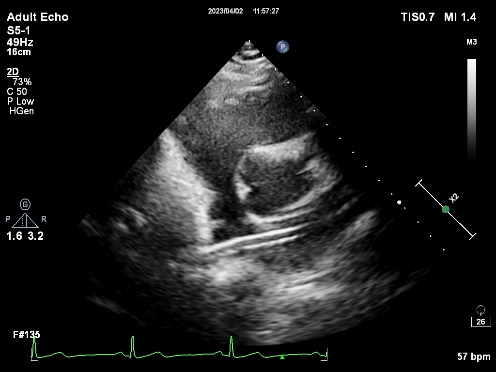

CDS放置在二尖瓣处

打开夹子,调整弹道,使其垂直于二尖瓣瓣环

将MitraClip™推进至左心室,并向上拉,直到瓣叶被抓捕

成功捕捉瓣叶后,经超声心动图反复确认瓣叶夹持牢固,释放瓣膜夹